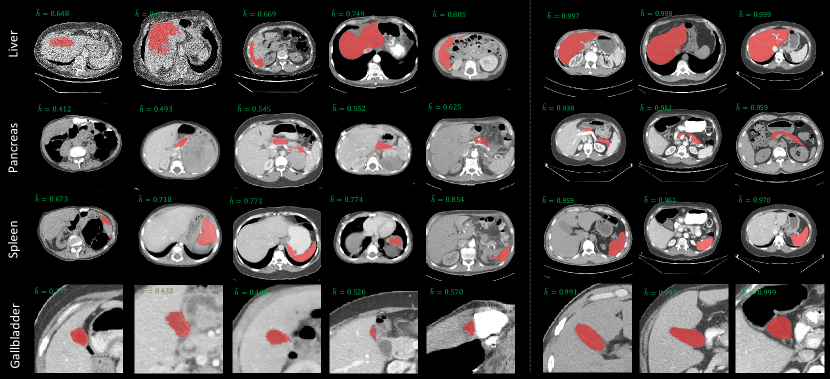

External Evaluation. Fig. 2 (a) showcases Quality Sentinel’s optimal predictions on its testing set, revealing a strong correlation between the model’s DSC predictions and actual values, underscoring the model’s predictive reliability. However, generalization risks remain since the model was developed on a single data source. We do external evaluations to validate its performance on more data domains. First, we use BTCV (Landman et al., 2015), a well-known manually annotated dataset with 13 classes, to show the model’s performance. As shown in Fig. 2 (b) and (c), we use morphological operations (i.e., erosion and dilation) to generate degraded masks and use Quality Sentinel to infer the DSC, showcasing consistent results with the testing set. Even though the LCC decreases to 0.850 and 0.775 in these two cases, this experiment validates the generalization of Quality Sentinel on out-of-distribution data and unseen mask degradation. We attribute this ability to the large-scale training dataset comprising a wide variety of different degradation modes. Second, we apply Quality Sentinel to the largest multi-organ segmentation dataset, AbdomenAtlas (Qu et al., 2024), to visually demonstrate the model’s ability to detect label errors. In Fig. 4, we show the model prediction of DSCs on four representative abdominal organs. On the left of the figure, imperfect labels with missing, overly expanded, and reduced masks are detected. On the right of the figure, it can be seen that high-quality masks are far smoother and more precise than imperfect masks.